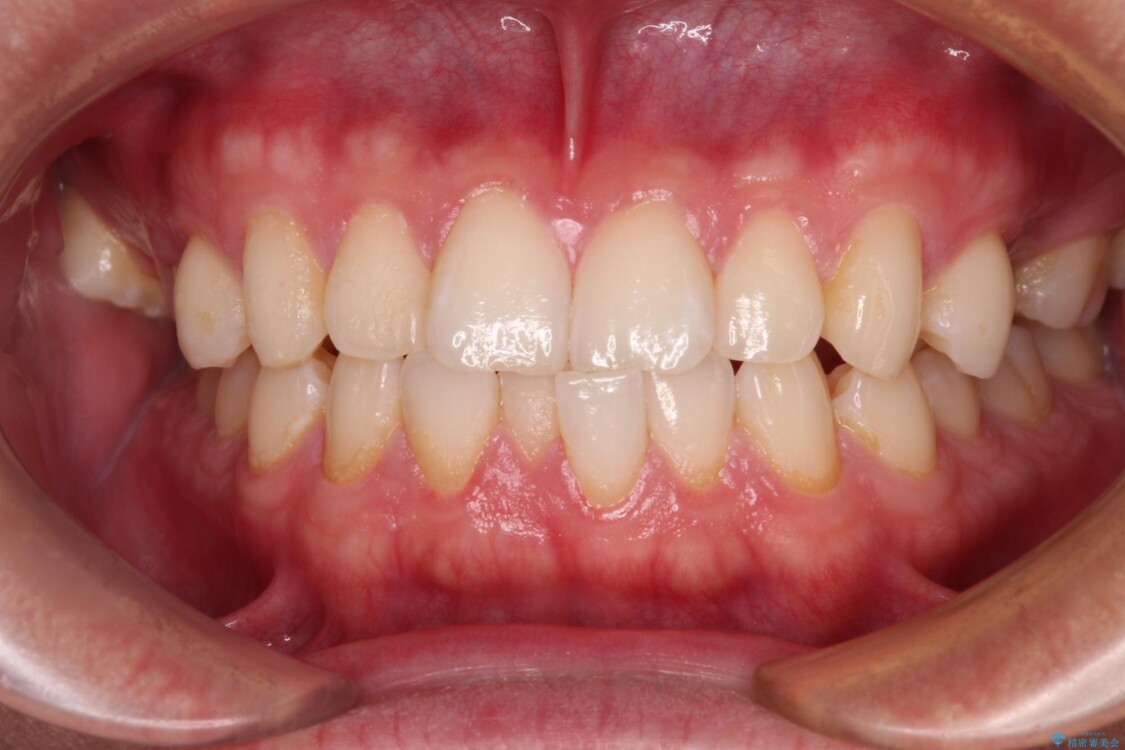

治療前

• 前歯のガタガタ・奥歯のかみ合わせ(シザーズバイト)を改善|1年半で完了したメタルブラケット矯正 治療前画像